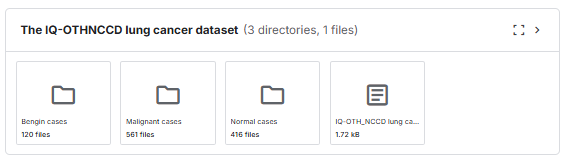

!unzip -q /content/the-iqothnccd-lung-cancer-dataset.zip압축을 풀게되먄 The IQ-OTHNCCD lung cancer dataset 가 생성됨

[ Begin - 시작되는단계, Malignat - 폐암, Normal - 일반인 ]

이렇게 시작, 폐암, 일반인으로 3가지의 분류가 되어있는것을 확인할 수 있습니다.

Bengin cases,Malignant cases,Normal cases디렉토리를 data 디렉토리 안으로 넣어주었습니다.

그래서 수동으로 끌어다 넣으면 경로가 완성이됩니다.

전체 파일리스트의 개수(416, 120,561)를 각각 cls list를 돌면서 각각 데이터를 넣어준것입니다.